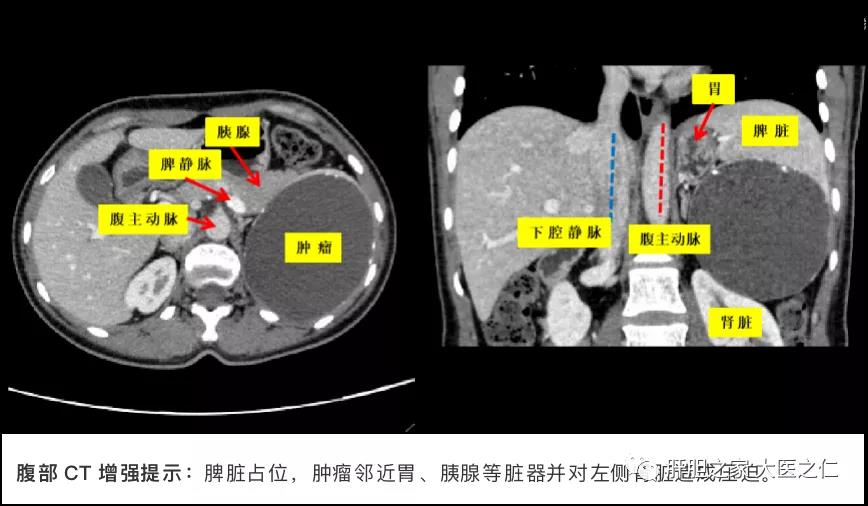

患者34岁,女性,因体检发现脾脏占位性病变半月余就诊于我院红角洲院区肝胆外科门诊,入院后完善相关检查,腹部CT提示脾脏囊性病灶并边缘多发钙化,肿瘤大小约为10.5cm×8.2cm×8.9cm。